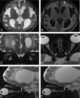

Perioptic hemorrhage

Optic nerve tram-track sign